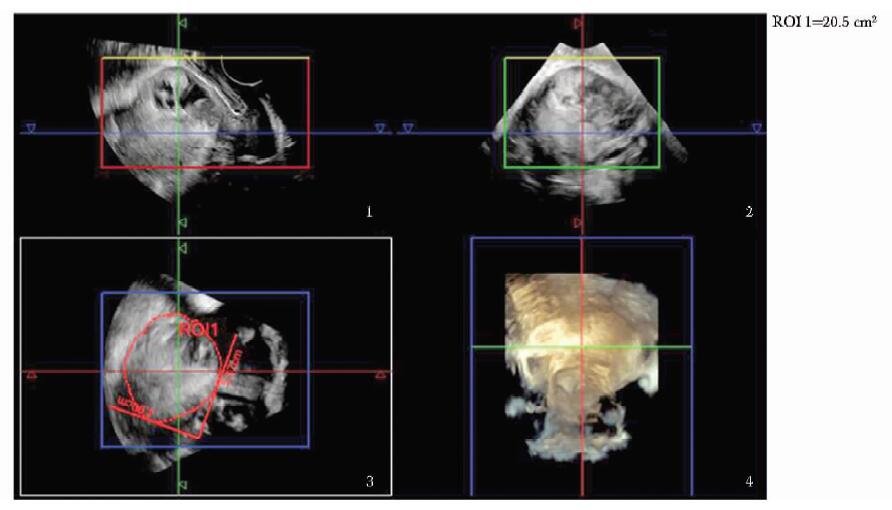

方法  收集2011年11月至2013年1月北京协和医院临床确诊为剖宫产切口瘢痕妊娠、并接受手术治疗的35例患者, 术前进行二维及三维超声检查, 获得病灶最大径、病灶平均径、病灶植入瘢痕面积、植入体积及植入深度; 按有无胎心搏动、病灶类型、彩色多普勒血流分级及术前有/无甲氨蝶呤联合治疗进行分组。记录患者手术中出血量, 分析超声参数与出血量的相关性, 比较组间出血量差异; 将病灶按出血量进行分组, ≥ 200 ml组和 < 200 ml组, 应用Logistic回归分析影响出血量的独立危险因素。

Methods  A total of 35 CSP patients who received operational treatment from November 2011 to January 2013 were enrolled in this study. The 2-and 3-dimensional ultrasound examinations were performed before the surgery, and the following parameters were recorded:maximum diameter of lesion(Dmax), average diameter of lesion(Dmean), implantation area of lesion(S), implantation volume of lesion(V), and implantation depth of lesion(Dimp). All these cases were divided into different groups according to the following characteristics separately:with/without fetal heart beat, lesion shown as gestational sac/mass, vasculature grade poor/median/rich, whetheror not combined with methotrexate(MTX) treatment prior to operations. The amount of bleeding during the operation was recorded. The correlation between the above parameters and the amount of intraoperative bleeding was analyzed. The bleeding amount of different groups was compared. Also, the patients were divided into two groups according to bleeding amount ≥ 200 ml and < 200 ml, and the potential independent risk factors of bleeding were analyzed using Logistic regression.